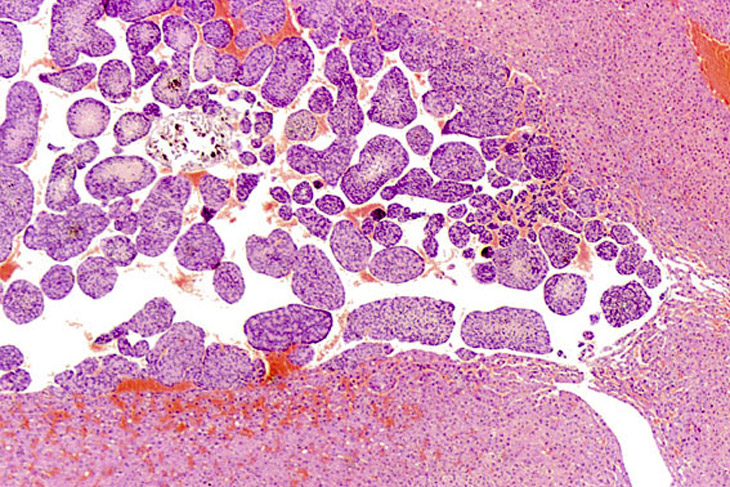

Hepatoblastomas and biliary cysts in the liver of an adult mouse.